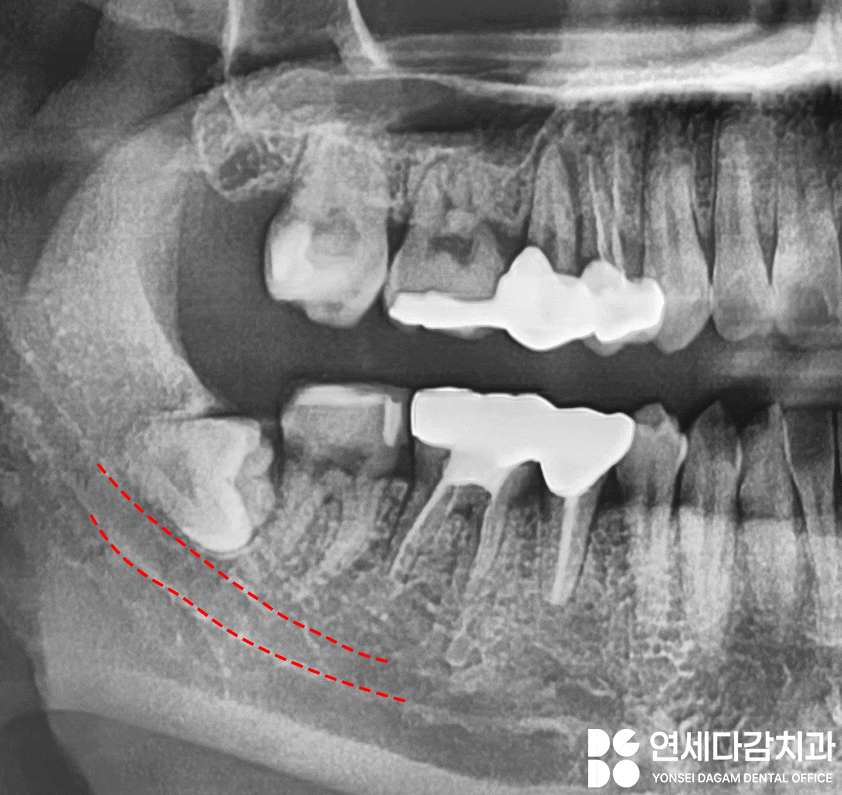

아래턱 사랑니 발치 시

주의해야 될 또 다른 중요한 구조물은

이것뿐만이 아닙니다.

수평으로 매복된 경우,

CT 분석 결과 하치조신경과

근접해 있는 경우가 많습니다.

하치조신경은 아래턱의

감각을 담당하는 주요 구조물이므로,

손상되면 감각이상이 생길 수 있습니다.

따라서 오금동 치과 에서 보여드린

해당 케이스에서도

극도로 조심스러운

접근이 필요합니다.

마찬가지로 사전 분석을 통해

치료 전략을 세우고,

계획에 따라 분할 발치를

시행하여 치아 조각이

남지 않도록 깔끔하게 치료를 완료합니다.